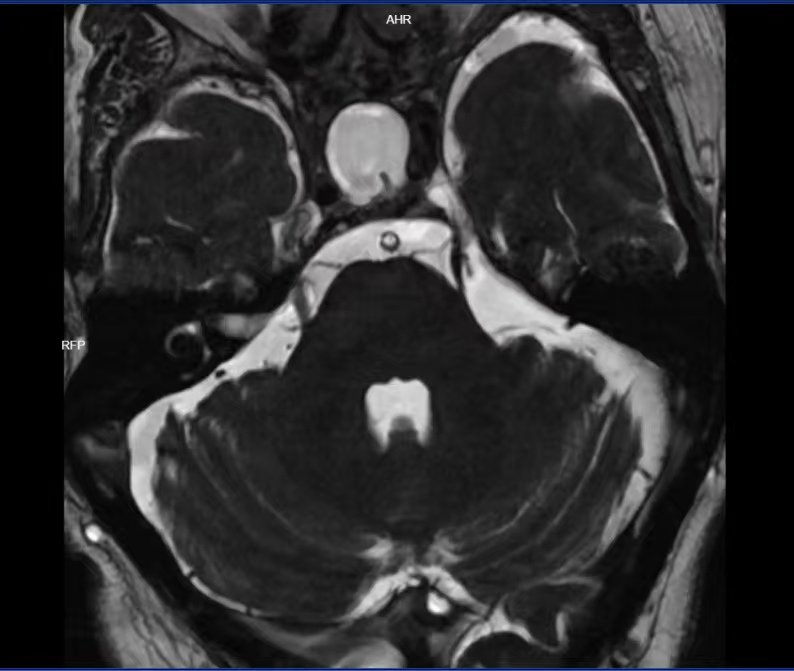

入院后,经完善相关检查,被明确诊断为左侧原发性三叉神经痛,手术指征明确。考虑到患者年事已高,手术风险相对较高,为最大限度保障手术安全,神经外科主任、主任医师肖炳祥组织全科医师开展病例讨论,对患者的病情、身体状况进行全面细致分析,最终制定了周密、精细化的手术方案——采用“神经内镜下左侧三叉神经微血管减压术”。

术中